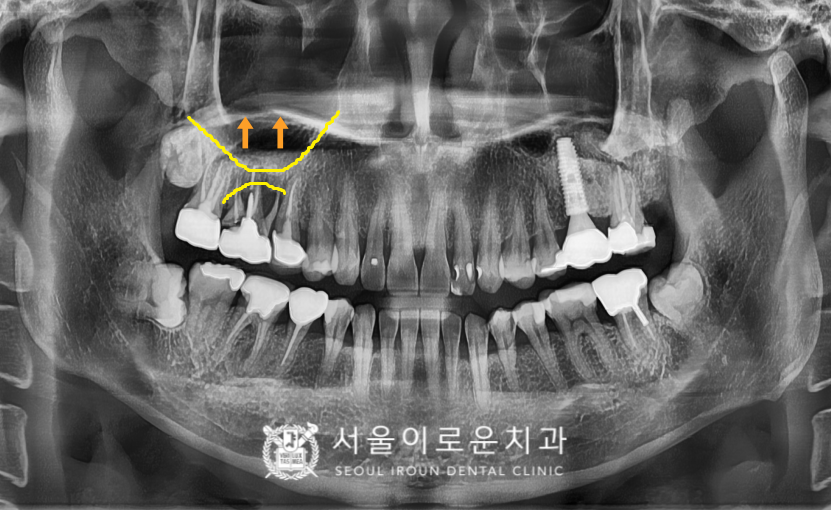

그리고 불편감을 호소하신

오른쪽 위턱 어금니 외에도

왼쪽 아래턱 송곳니(#33)와

바로 뒤 첫 번째 작은 어금니(#34)는

치아 사이 부분에서 충치가 관찰되었는데요.

충치의 범위와 진행 정도,

치아 검사를 통해

송곳니(#33)은 레진 치료,

첫 번째 작은 어금니(#34)는

신경치료 후 크라운 수복을

진행하기로 하였습니다.